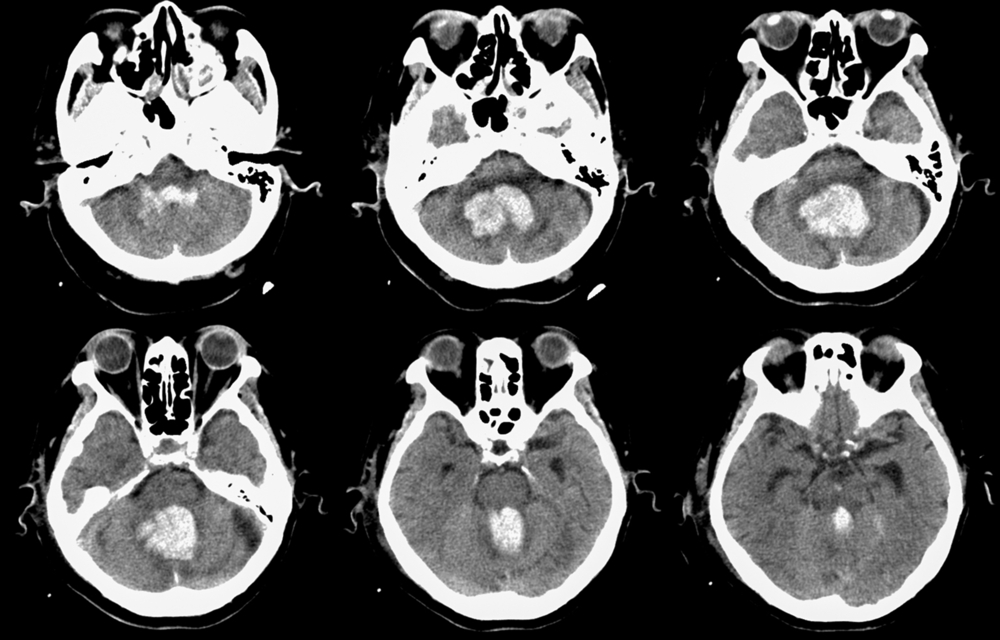

Диагностика

Для постановки диагноза нужно учитывать жалобы пациента, причины, после которых возникли гематомы. В некоторых случаях постановка диагноза не вызывает трудностей, если после травмы сразу появились яркие симптомы. В этом случае при осмотре врач обнаружит синяк и припухлость тканей. Важным критерием являются данные о светлом промежутке. Диагноз обязательно подтверждают инструментальными методами:

- Компьютерная томография – определяет изменения плотности участков головного мозга, объем и форму гематомы.

- МРТ головного мозга – позволяет получить изображение структуры мозга.

- Церебральная ангиография – отображает смещение сосудов при наличии сгустка крови.

- Рентгенография – дает сведения о повреждениях костей черепа.

Дополнительно может потребоваться эхоэнцефалография, которая помогает определить нарушения в проведении нервного импульса.